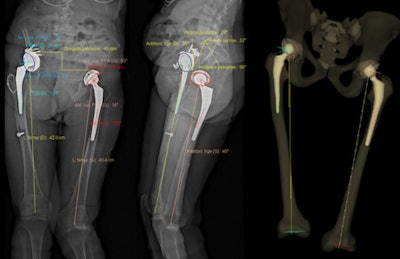

"In a single acquisition period, this 3D SR system also determined the valgus and varus measurements of the weight-bearing lower limbs. This too should reduce the patients' medical irradiation a little more, by avoiding the need for other medical imaging," noted lead author Dr. Cyrille Delin, from the Réseau d'Imagerie Médicale Maussins-Nollet in Paris. "The use of the SR system to study the torsion of lower limbs makes it possible to reduce the amount of medical irradiation that patients accumulate."

"Lower limb torsion values (anteversion of femoral necks or torsion of the knees or legs) play a role in the functioning of these limbs and in the development of osteoarthritis of the hip," they stated. "These values must be measured before placement of hip or knee prostheses but also before osteotomies for femoral or tibial correction of bone calluses or dysmorphisms. They are also useful before surgical revision of hip and knee prostheses in cases of poor positioning, given the frequent imprecision of surgeons' intraoperative evaluation of prosthetic femoral anteversion."